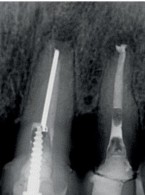

Zgłosiła się do mnie 60-letnia pacjentka z nieszczelną i nieestetyczną koroną protetyczną osadzoną na zębie siecznym szczęki. Pacjentka poinformowała, iż ząb był poddany przed laty zabiegowi resekcji. Wykonane zdjęcie potwierdziło wcześniej wykonaną apikotomię oraz obecność niewielkich zmian zapalnych w tkankach okołowierzchołkowych. W kanale stwierdzono dobrze kontrastujący się ćwiek (prawdopodobnie srebrny); w części koronowej kanału był widoczny krótki indywidualny wkład koronowo korzeniowy. Co mogę zasugerować pacjentce? Jakie są możliwości leczenia?